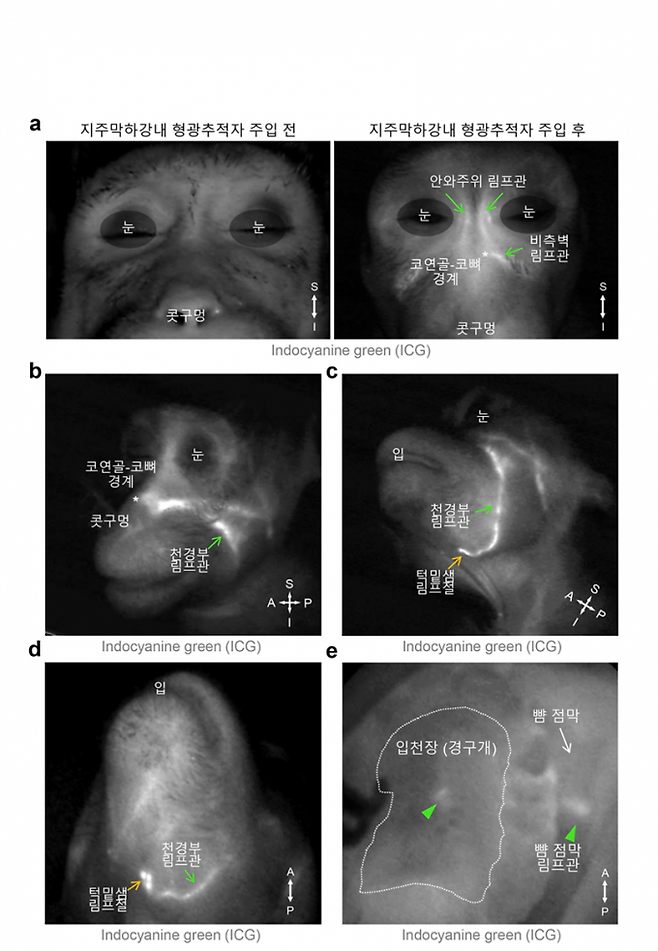

연구팀은 림프관에 선택적으로 형광 표지자를 발현하는 생쥐 모델과 생체 내 이미징 기술 등 첨단 시각화 기술을 활용해 뇌척수액 배출 경로를 시각화했다. 그 결과 뇌척수액이 눈 주위, 코안 쪽 그리고 입천장의 림프관을 통해 얼굴 피부 아래, 주로 눈·코 옆 림프관으로 모인 뒤 턱밑샘 림프절로 배출됨을 규명했다.

공동 제1저자인 진호경 IBS 선임연구원은 “한국생명공학연구원 국가영장류센터 이영전 박사 연구팀과 협업을 통해 이번에 발견한 뇌척수액 배출 경로가 쥐뿐만 아니라 영장류에도 존재함을 확인했다”며 “이는 사람에게도 유사한 뇌척수액 배출 경로가 존재할 가능성을 강력히 시사한다”고 말했다.